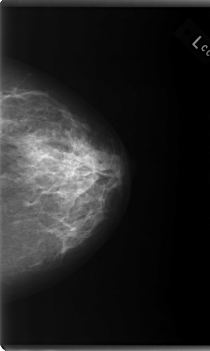

C_0095_1.LEFT_CC

LEFT_CC LINES 5960 PIXELS_PER_LINE 3568 BITS_PER_PIXEL 12 RESOLUTION 50 NON_OVERLAY